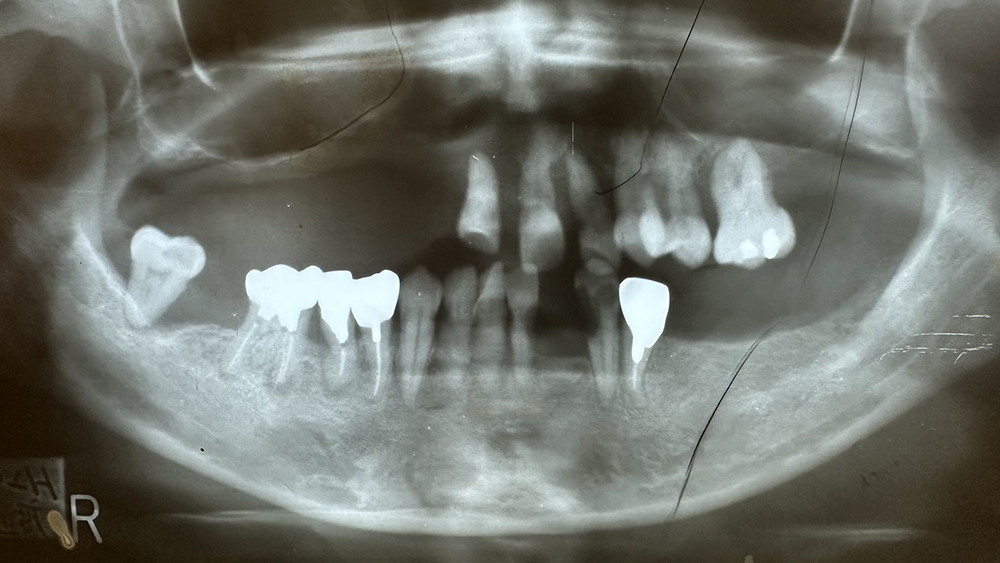

症例1

Before

After

非喫煙、碧南の陶芸家 70代男性

治療の期間・回数:①約7か月 ②約8か月 ③5か月

治療の価格:①2,200,000円 ②約8,000,000円 ③約300,000円

治療内容:この方は平成22年に初めて来院されました。

①他院で下あごの奥歯にインプラント治療を受けていましたが、上あごは「できない」と言われたそうです。当院では上あごに7本のインプラントを入れ、その日のうちに仮のブリッジを装着しました(即時荷重)。

②令和元年には、左上の奥のインプラントが抜けてしまったため、骨を足す手術(サイナスリフト)を行い、同時に2本のインプラントを追加しました。その半年後に、以前のブリッジを修理して再利用しています。

③さらに令和3年には右下の奥歯が折れてしまったため、インプラントを1本追加しました。当院では再治療や追加治療の場合、費用は2割引きとしています。

現在、上あごのブリッジは「コバルトクロム合金+セラミック」で作られた、スクリューでしっかり固定するタイプです。精度が高く、長く安定させるために、このような固定方法が望ましいと考えています。